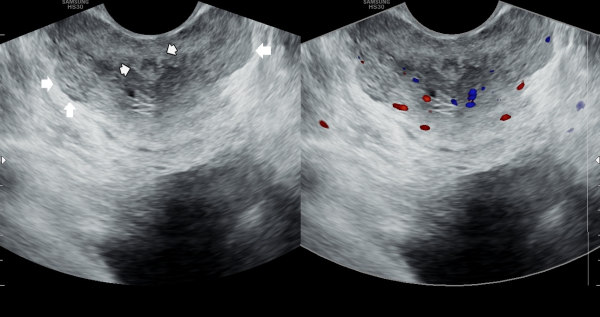

오래전부터 배뇨장애와 빈뇨 및 급박뇨등으로 다른 비뇨기과에서 약물 투여를 했으나 증상의 호전이 없다고 내원 당일 검사한 고환내 다량의 미석증이 관찰된 초음파 사진입니다.

This is an ultrasound image taken on the day of the patient’s visit, who reported long-standing urinary symptoms such as voiding difficulty, frequent urination, and urgency, with no improvement despite medication from other urology clinics. The scan shows a large amount of microcalcifications within the testes.

The ultrasound image on the left shows the initial examination, where testicular microlithiasis (tiny calcifications) was present.

The ultrasound image on the right is a follow-up study after several months of targeted therapy to the vas deferens, ejaculatory ducts, seminal vesicles, and prostate, twice a week.

The follow-up scan demonstrates that the previously noted microlithiasis has improved, suggesting that the targeted treatment contributed to the restoration of testicular health.

We hope this evidence may help inform colleagues and patients worldwide that such cases of testicular microcalcification, associated with chronic prostatitis or seminal tract obstruction, can improve through this approach.